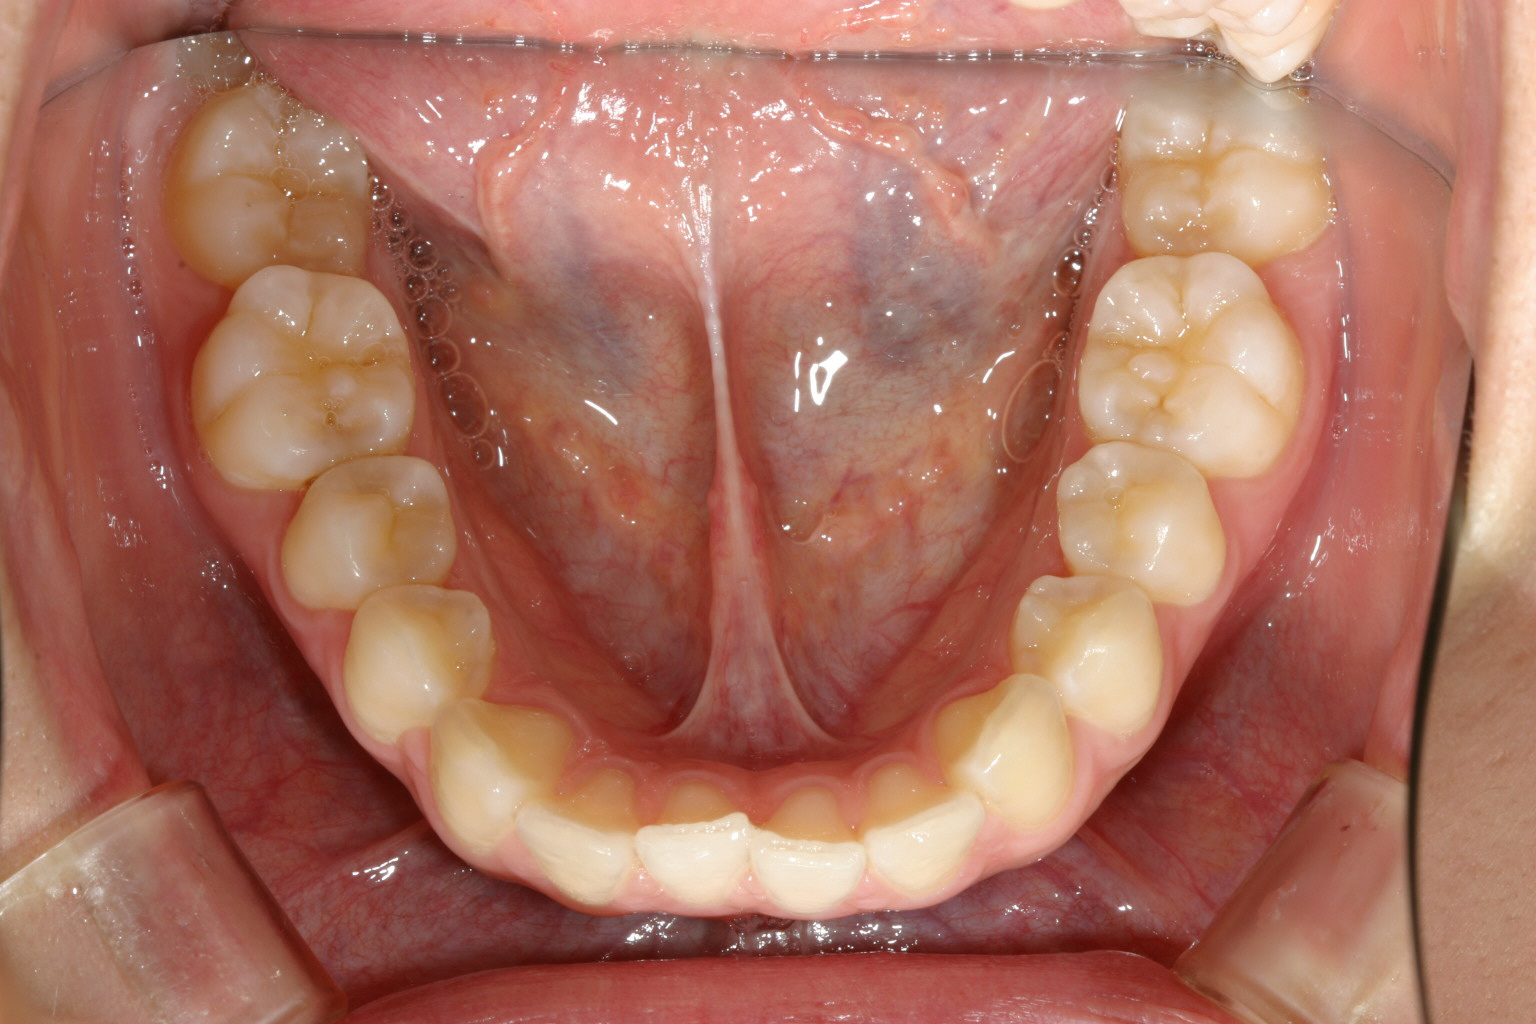

下顎は少し乱れてますがさほどでもないです。

こちらも綺麗なアーチになりました。